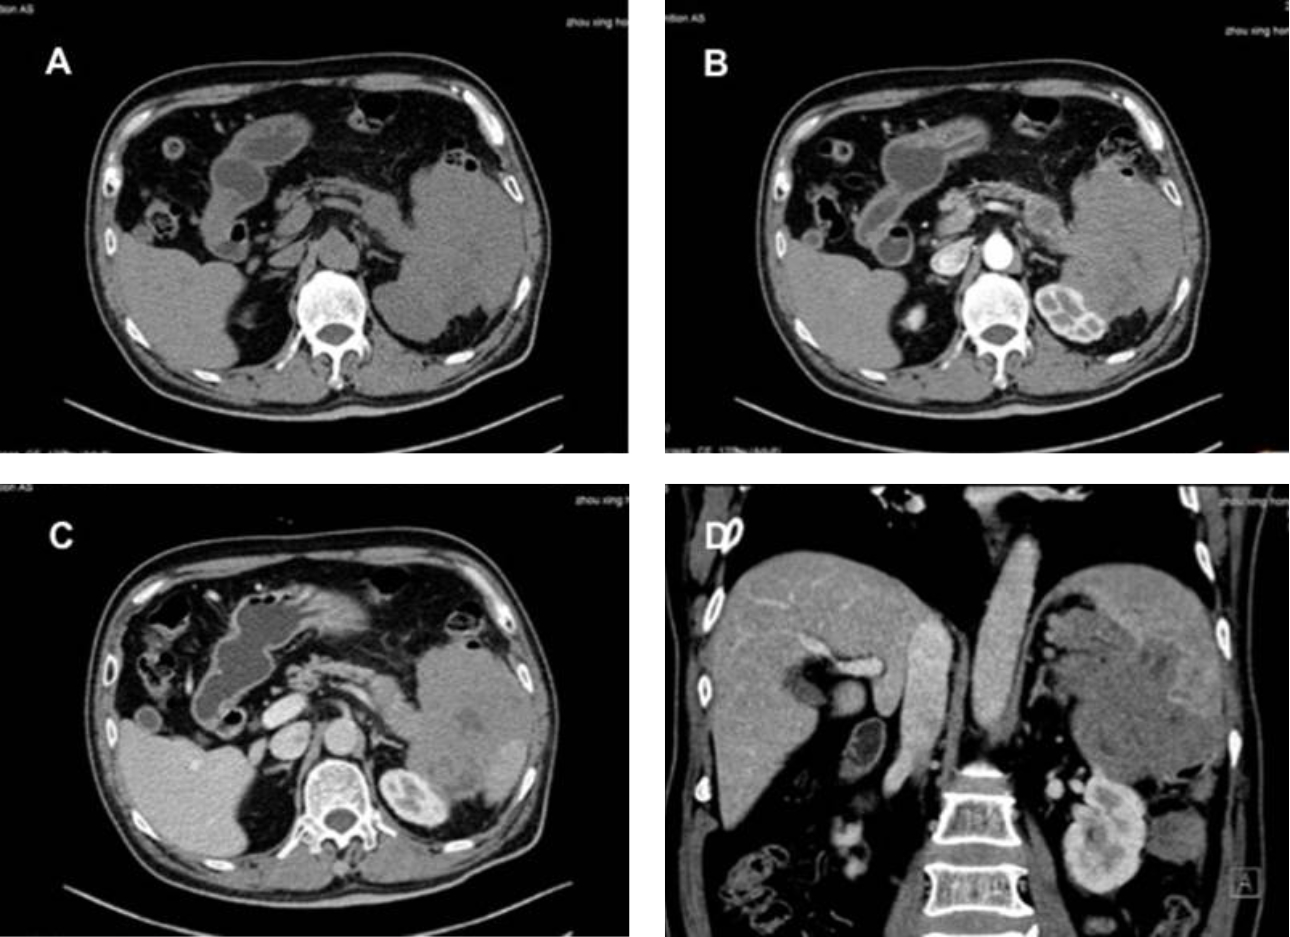

??? US, CEUS, CT ? ?? PET/CT ??? ???? ? ??? Fig 1-3? ????.

??? ?????? R-Hyper-CVAD-A ????? ???? ??? CT ??? ?? ?? ??? ??? ??? ?? ?? ? ? ????. (Fig 4 A-C). ??? ???? ??? ?? ??? ??????.